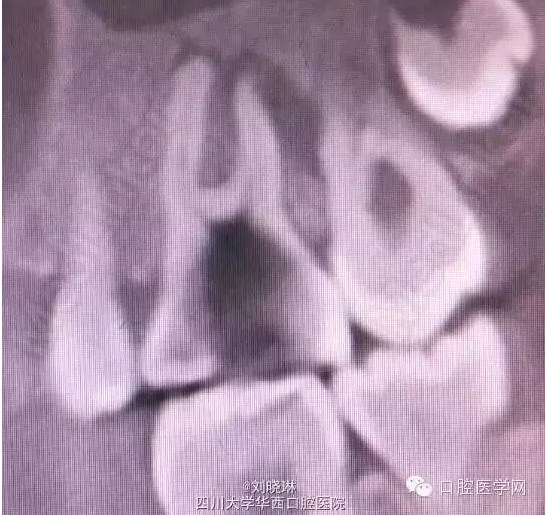

CBCT示:16牙合面大面積牙體組織密度減低影,與髓腔穿通,腭側(cè)根管內(nèi)可見高密度影像,超出根尖孔外至上頜竇,根尖周組織暗影。